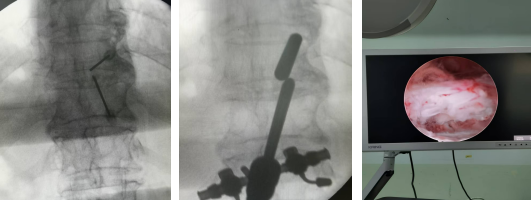

患者,女,82歲,T10/11黃韌帶鈣化并椎管狹窄,且伴有嚴(yán)重的骨質(zhì)疏松,術(shù)前雙下肢麻木、無力,不能正常行走。如果實施開放性手術(shù)需行全身麻醉下全椎板切除減壓內(nèi)固定治療,由于患者年齡大、耐受差,手術(shù)失敗率極高,經(jīng)過科室討論后決定給予微創(chuàng)手術(shù)治療。手術(shù)由郝清海副主任醫(yī)師主刀,在劉濤副主任醫(yī)師配合下順利完成UBE內(nèi)鏡下的黃韌帶鈣化物去除,椎管擴(kuò)大,脊髓減壓治療。手術(shù)切口約1.5cm,且能保留患者的運動單元,術(shù)后患者無明顯腰背痛癥狀,神經(jīng)功能有極大恢復(fù),可自主下地行走,療效確切,患者及家人對手術(shù)效果非常滿意。

術(shù)中定位、植入UBE內(nèi)鏡及內(nèi)鏡下減壓完成后脊髓膨隆情況

術(shù)中操作脊柱內(nèi)鏡